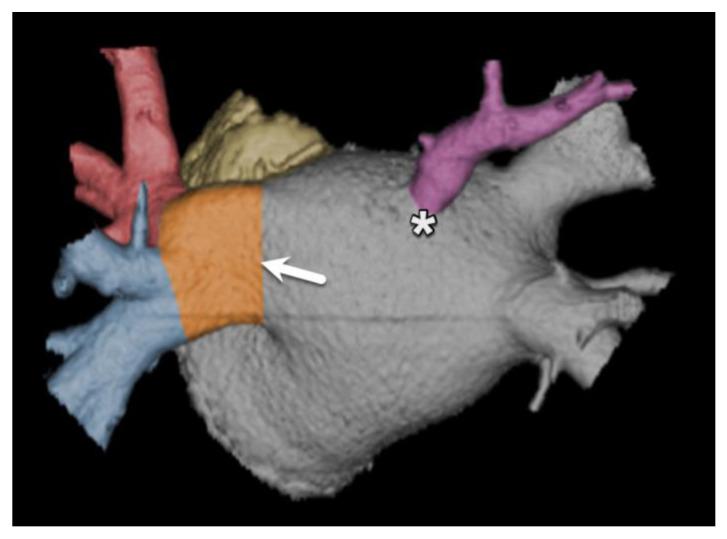

在过去十年中,多项试验和观察性研究证实,微创心脏介入治疗作为各种心脏病的可行治疗选择是有效的。在某些患者群体中,用于严重主动脉瓣狭窄的经导管技术已迅速成为外科主动脉瓣置换术的替代方法。此外,针对影响其他心脏瓣膜(如二尖瓣)的病症,非手术治疗选择也有所增加。这些新兴的微创介入治疗补充了已成熟的血管内技术,用于治疗心房颤动患者的房间隔缺损封堵、左心耳封堵和肺静脉隔离等疾病。鉴于这些手术的非手术性质以及缺乏对目标解剖结构的直接可视化,这些手术严重依赖精确的术前放射影像学检查,以实现最佳的患者选择和手术成功。本文基于作者的专家意见和详尽的文献研究。本手稿回顾了最常用的微创心脏介入治疗,强调了术前成像的基本信息以及放射学报告中必须包含的关键方面,以减少潜在并发症。准确的术前成像对于确保微创心脏介入治疗的安全有效至关重要,这突出了放射科医生在这些患者术前检查中的重要性。